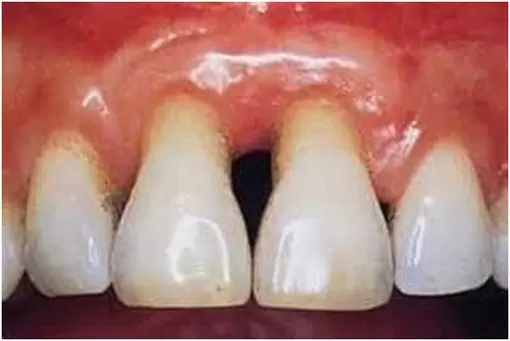

When gingivitis is not treated, it can advance to “periodontitis” (which means “inflammation around the tooth”). In Periodontitis, gums pull away from the teeth and form spaces (called “pockets”) that become infected. If not treated, the bones, gums, and tissue that support the teeth are destroyed. The teeth may eventually become loose and have to be removed.